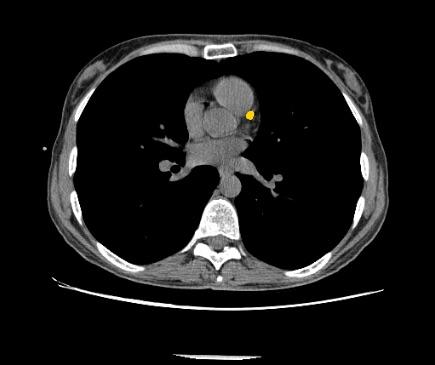

July 12, 2018 — Zebra Medical Vision has received 510(k) clearance from the U.S. Food and Drug Administration (FDA) for its Coronary Calcium Scoring algorithm. The algorithm, capable of automatically calculating a patient’s Agatston equivalent coronary calcium score from an electrocardiogram (ECG)-gated computed tomography (CT) scan, provides physicians with important data used in the assessment of the risk for coronary artery disease.

Coronary artery disease (CAD) is a major cause of death in developed countries. It remains responsible for approximately one-third of all deaths of individuals aged over 35 years old. According to estimates, nearly one-half of men and one-third of women over 40 years old will develop some symptoms of CAD in the United States. Numerous studies have shown that early detection and treatment of CAD can reduce the incidence of heart attacks in at-risk populations. Studies have also shown that coronary artery calcium score is useful for risk stratification of patients.